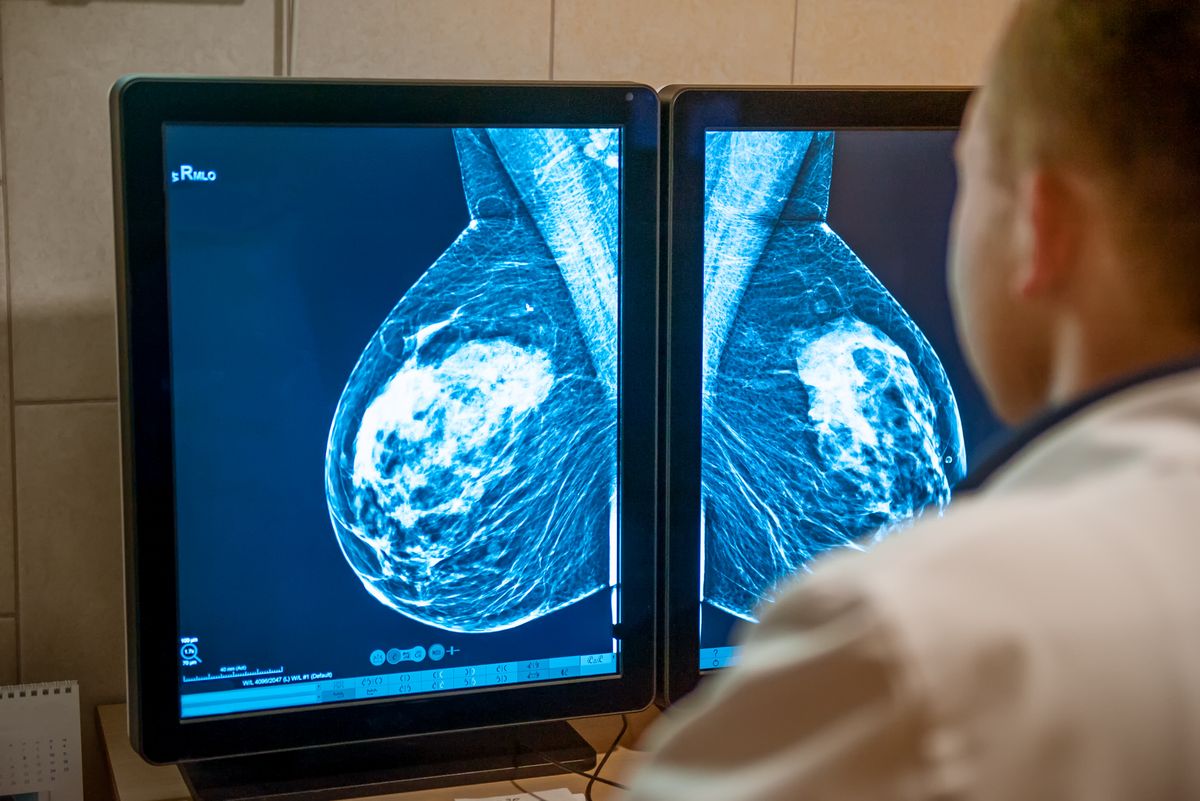

Jyllandsposten bringer i dag en artikel om et forskningsprojekt fra Aarhus Universitet, Institut for Folkesundhed, vedrørende brystkræftscreening. Konklusionen på projektet er, at gevinsten ved at indkalde alle kvinder mellem 50 og 70 år til brystkræftscreening hvert andet år efterhånden er så lille, at Danmark om kort tid bør stoppe det danske screeningsprogram for brystkræft.

Dansk Brystkræft Organisation må på det kraftigste advare mod at overveje at stoppe screeningsprogrammet. Derudover medfører kommunikation om evt. at stoppe screeningsprogrammet en stor risiko for, at danske kvinder ikke benytter sig af tilbuddet om screening.

Forskerne bag undersøgelsen fra Aarhus Universitet refererer til studier, der viser, at hver femte kvinde mellem 50 og 70 år, der i forbindelse med screening får at vide, at de har brystkræft, bliver overdiagnosticeret og herefter overbehandlet. Til dette siger Anja Skjoldborg Hansen: ”Det, der fortsat må være afgørende for behandling af kræft, må være, at den opdages så tidligt som muligt. Behandlingen vil hermed være mere skånsom, end hvis kræften først opdages, når den har udviklet sig. Derudover vil risikoen for overbehandling i patienternes øjne mere end opvejes af den nedsatte risiko for at dø af kræft. Der er jo ingen, der i dag kan forudsige, hvem der skal dø og hvem der ikke skal dø af brystkræft, når man finder en lille knude med kræftceller ved screening.”